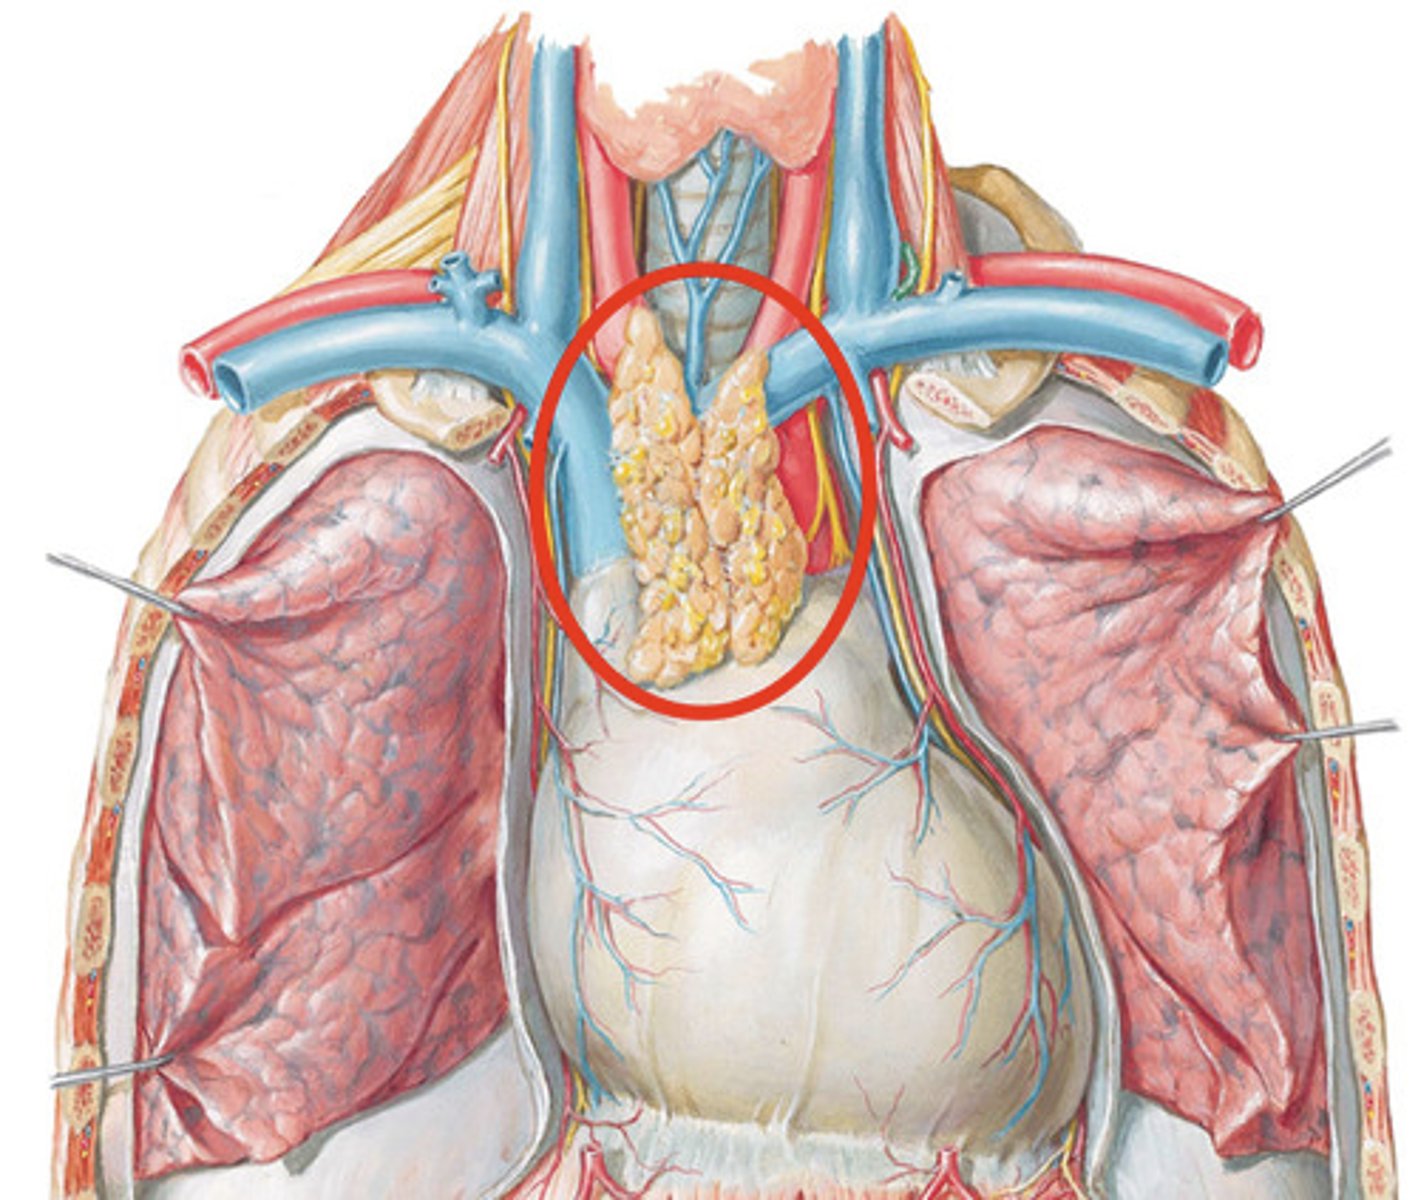

T cells

A type of lymphocyte that is created in the thymus; produce substances that attack infected cells in the body, provide acquired immunity

Central (primary) lymphoid tissues

where lymphocytes are formed and mature, bone marrow and thymus

What does the thymus do?

Site of T cell differentiation and maturation